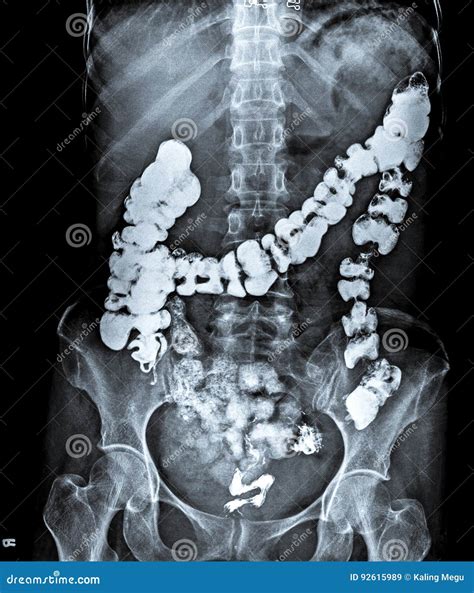

An X-ray for abdomen is a medical imaging procedure that uses a small, controlled amount of ionizing radiation to create images of the structures within your abdomen. The abdomen contains vital organs such as the stomach, intestines, liver, spleen, and kidneys. By passing radiation through the body, a specialized camera captures images that allow physicians to view these structures in black and white.

Once the images are taken, they are sent to a radiologist, who is a doctor specialized in interpreting medical imaging. The radiologist will look for specific markers on the film, such as:

• Gas patterns: An abnormal distribution of gas in the intestines can indicate a blockage.

• Radiopaque densities: These appear as bright white spots and often signify kidney stones or ingested objects.

• Air outside the bowel: This is a serious finding indicating a potential perforation that requires urgent surgery.